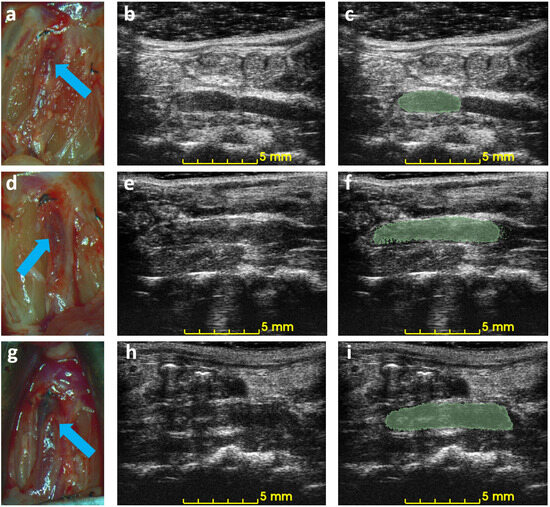

Figure 5 shows the correlation between ultrasound volume and macroscopic observation. The volume of blood clots segmented from 3D ultrasound acquisition in mice ( N = 10 ) ranged from 5.3 to 20.0 mm 3 , and the mean volume was 13.5 mm 3 . Meanwhile, the cylindrical volumes of the macroscopic measurements ranged from 5.0 to 29 mm 3 after removing the mean thickness of the vein wall of 105 μ m from the macroscopic measurement. The correlation coefficient R 2 is 0.91. The root mean square error for this linear regression is 2.51 mm 3 . Three examples of ultrasound imaging slices and their corresponding photos are shown in Figure 6. The thrombi are indicated with arrows in macroscopic observations and highlighted with light-green masks in ultrasound imaging, shown in Figure 6.

Figure 6. Example of macroscopic photos and ultrasound imaging on day 3. Each row is the macroscopic photo (a,d,g), the ultrasound image (b,e,h), and the ultrasound image with an overlaid mask of the blood clot (c,f,i) of each mouse. Arrows indicate the location of the detected blood clots in macroscopic photos.